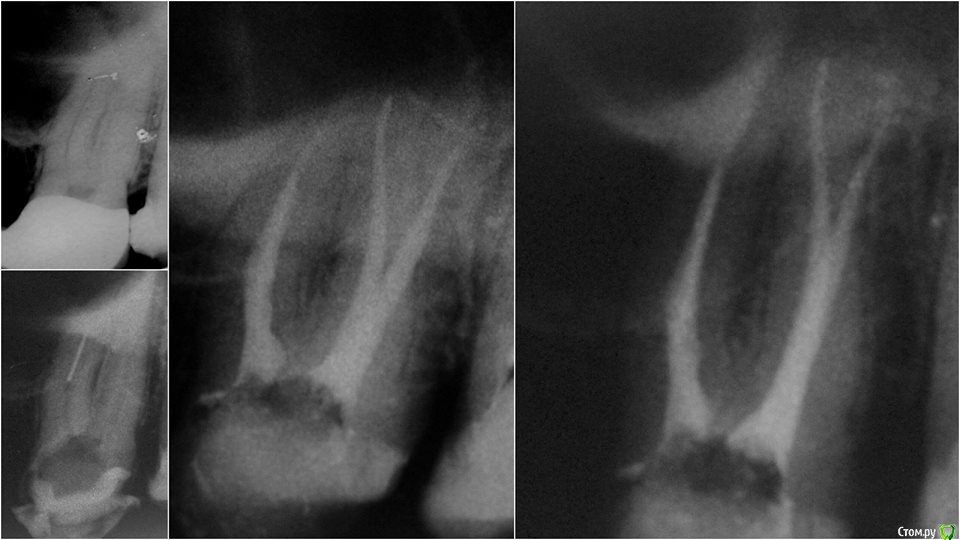

Romanson Опубликовано 5 мая, 2015 Поделиться Опубликовано 5 мая, 2015 (изменено) Уважаемые коллеги, гуляя по просторам facebook'a наткнулся на этот кейс.Не могу понять, какой принцип у этого девайса? Каким образом используется эта петля в игле? Объясните пожалуйста...Фото Gergely Benyőcs Изменено 5 мая, 2015 пользователем Romanson Ссылка на комментарий

anvladd Опубликовано 5 мая, 2015 Поделиться Опубликовано 5 мая, 2015 (изменено) Я так понимаю накидывается как петля на шею) ,на отломок и тянется. Изменено 5 мая, 2015 пользователем anvladd Ссылка на комментарий

Romanson Опубликовано 5 мая, 2015 Автор Поделиться Опубликовано 5 мая, 2015 К этому девайсу обязательно нужен микроскоп и очень прямые рукиЭто понятно, без второго вообще ни один девайс работать не будет Я так понимаю накидывается как петля на шею) ,на отломок и тянется.Точно! Не заметил петлю на этом фотоГде такую проволоку тонкую (0.05) купить? В обычных бытовых магазинах спрашивать? Ссылка на комментарий

Kolchanov Опубликовано 5 мая, 2015 Поделиться Опубликовано 5 мая, 2015 А Колчанов умеет и без скопа Это что, фан-клуб? Вы ошибаетесь, я иголками еще ни одного отломка не достал. Да и вообще чаще получается так, что они остаются в каналах. Мне вообще кажется, что такой уже освобожденный кусок и сам бы выскочил без всяких иголок. 4 Ссылка на комментарий

Romanson Опубликовано 6 мая, 2015 Автор Поделиться Опубликовано 6 мая, 2015 Это что, фан-клуб? Вы ошибаетесь, я иголками еще ни одного отломка не достал. Да и вообще чаще получается так, что они остаются в каналах. Мне вообще кажется, что такой уже освобожденный кусок и сам бы выскочил без всяких иголок. Тоже так подумал, что если уже есть возможность на отломок иглу с петлей накинуть, то обычный уз справился бы с этой задачей не хуже. Возможно, этот метод применяется для отломков агрессивных инструментов, когда освободив даже больше половины отломка он не выкручивается и не вылетает?.. Ссылка на комментарий

anvladd Опубликовано 6 мая, 2015 Поделиться Опубликовано 6 мая, 2015 не порвется ли эта проволока если отломок хорошо "засел"? Ссылка на комментарий